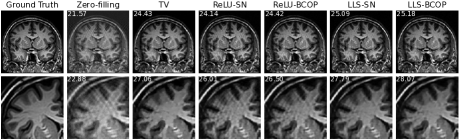

Section 5 is devoted to the application of our framework to the problem of biomedical image reconstruction. Our approach revolves around the design of a robust 111-Lipschitz CNN for image denoising that mimics the architecture of DnCNN ZZCMZ2017 —a very popular image denoiser. The important twist is that, unlike DnCNN, the convolution layers of our network are constrained to be Parseval, which makes our denoiser compatible with the powerful plug-and-play (PnP) paradigm for the resolution of linear inverse problems Chan2016plug ; Kamilov2023plug ; Sun2021 ; Venkatakrishnan2013plug . We first provide mathematical support for this procedure in the form of convergence guarantees and stability bounds. We then demonstrate the feasibility of the approach for MRI reconstruction and report experimental results where it significantly outperforms the standard technique (total-variation-regularized reconstruction) used in compressed sensing.